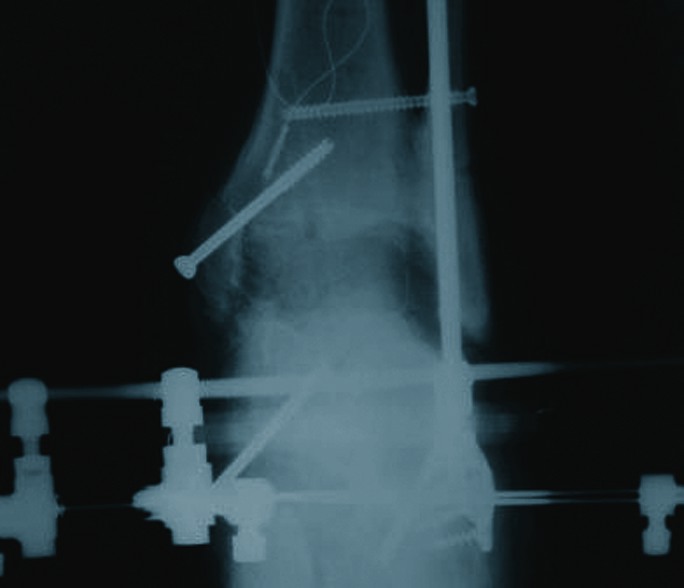

Case Study: When An Ankle Implant Arthroplasty Fails

In this case, a patient presented with significant failure of a previous ankle implant arthroplasty. In the above photo, note the valgus and subsidence of the talar component. One can also see the loosening of the tibial component and the probable non-union of the syndesmosis.

The surgeons used an isolated medial approach. Note the large defect after removal of the implant in the above photo.

As one can see in the above photo, the arthrodesis interface biologics include an implantable bone stimulator, fresh frozen femoral head allograft and demineralized bone matrix (DBM).

The above photo shows a one-week post-op radiograph with external fixation.

Note the final consolidation at six months postoperatively in the above photo.

(Photos courtesy of Glenn Weinraub, DPM, FACFAS)